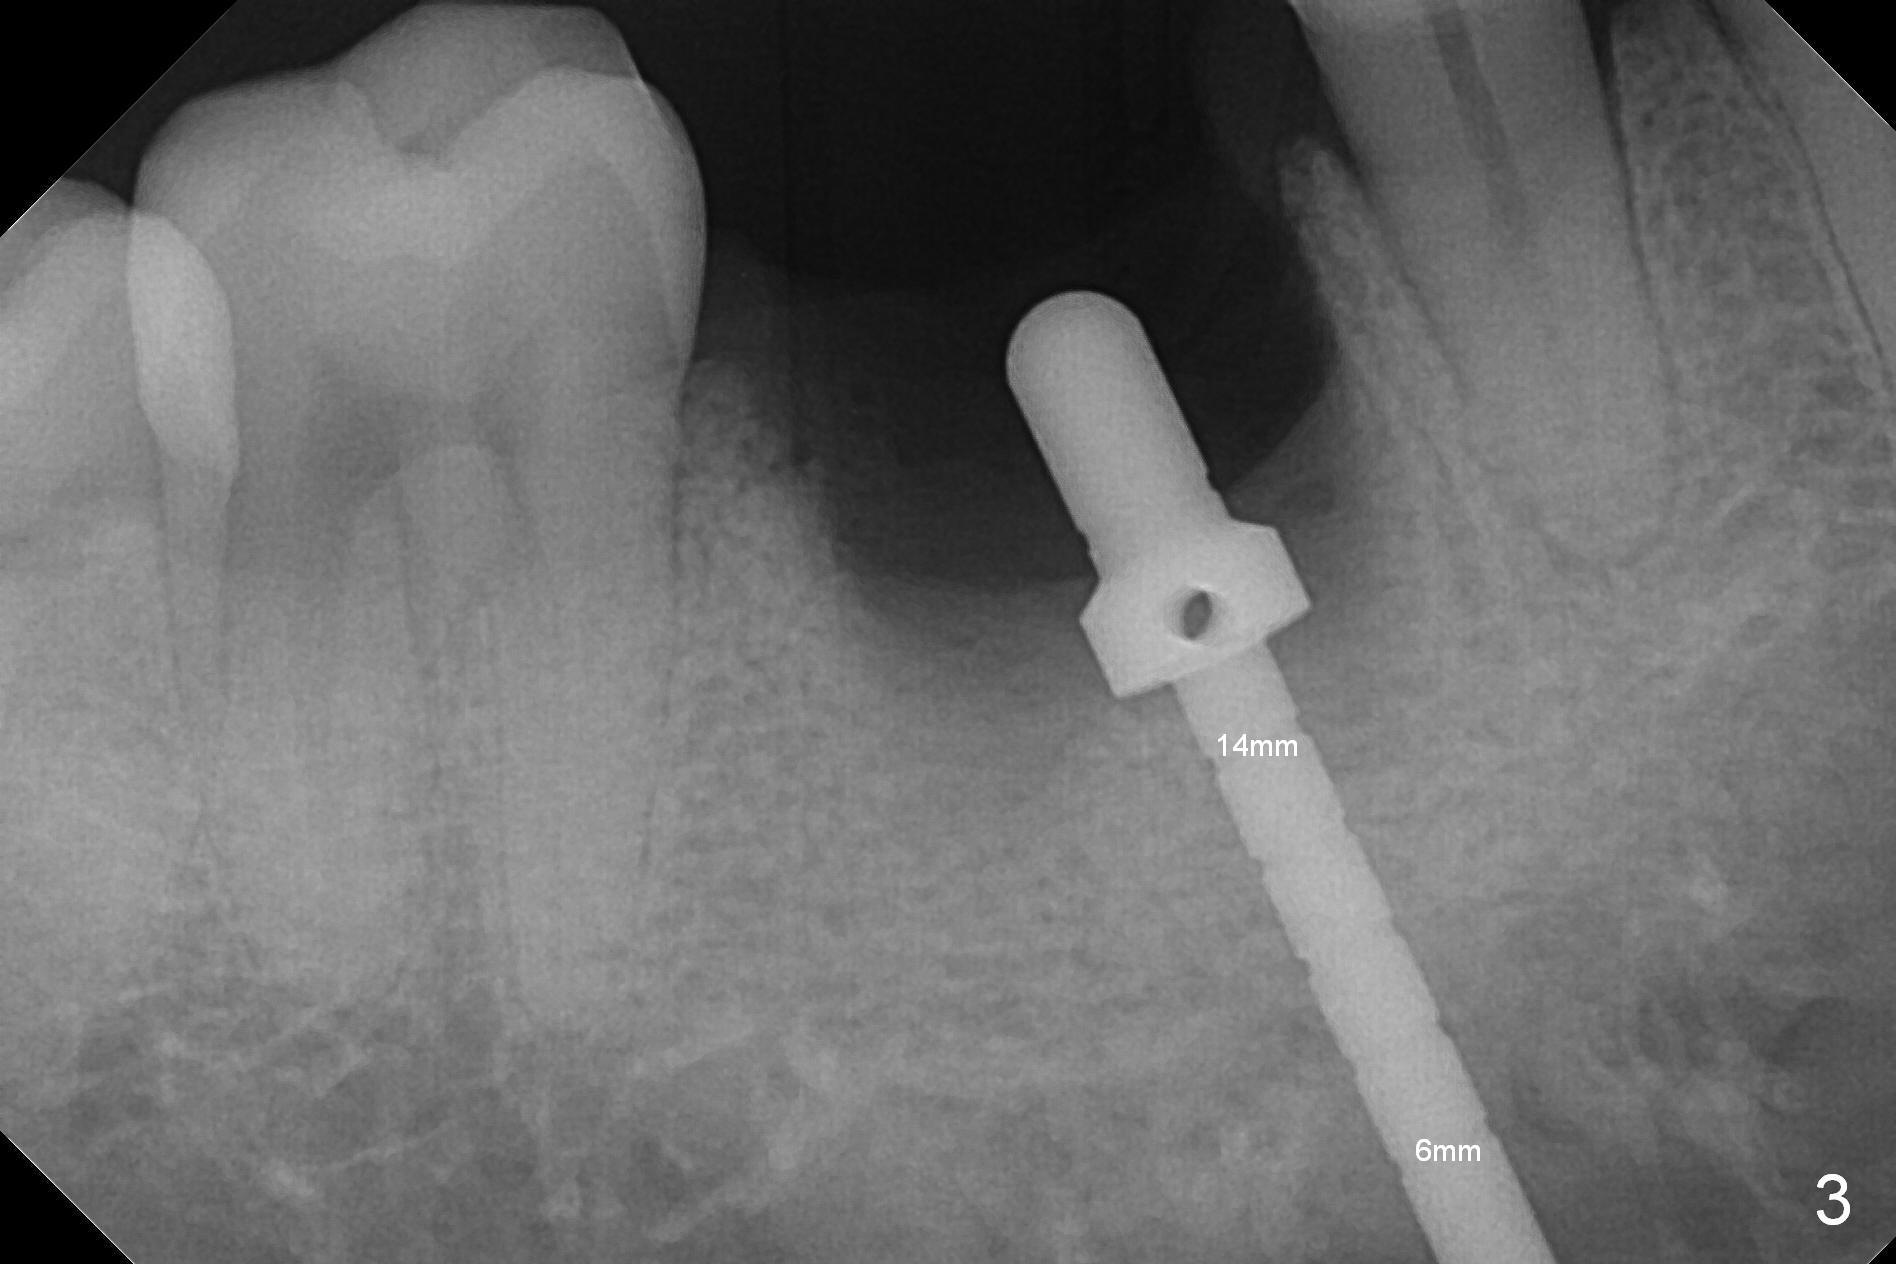

After extraction of the tooth #30 with Class V furcation involvement (Fig.1 (>),2 (L: lingual)), initial osteotomy depth is 8 mm with infiltration anesthesia, but a parallel pin is able to be inserted for 16 mm without pain (Fig.3). There is oozing from the osteotomy. Osteotomy increases in diameter with depth at 8 mm (Fig.4 (3.8 mm drill),5 (5.3 mm tap)). As the Inferior Alveolar Canal (IAC) is indistinct with increased pain during osteotomy, a 5.9x6 mm implant is placed with >50 Ncm following Septocaine infiltration (Fig.6). When bone graft (Fig.7 *) and 7.8x5.5(6) mm abutment (Fig.7,8) are placed, panoramic X-ray is taken (Fig.9). There appears to be a thick layer of spongy bone in the posterior mandible between the red and yellow dashed lines (Fig.5,9). Panoramic X-ray and/or CBCT should be taken if preop PA does not reveal IAC. This patient seems to be a bruxer. There are mandibular tori. Bone loss (furcation involvement) is not proportional to his oral hygiene status. Functional loading (progressive) should be delayed due to bruxism and the short implant.